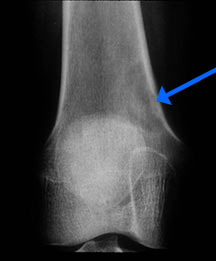

- May arise from any bone and any site within a bone (epiphyseal, metaphyseal, diaphyseal)

- Radiographically variable appearance: may appear benign (geographic) or malignant (permeative or moth eaten)

Radiographic Presentation